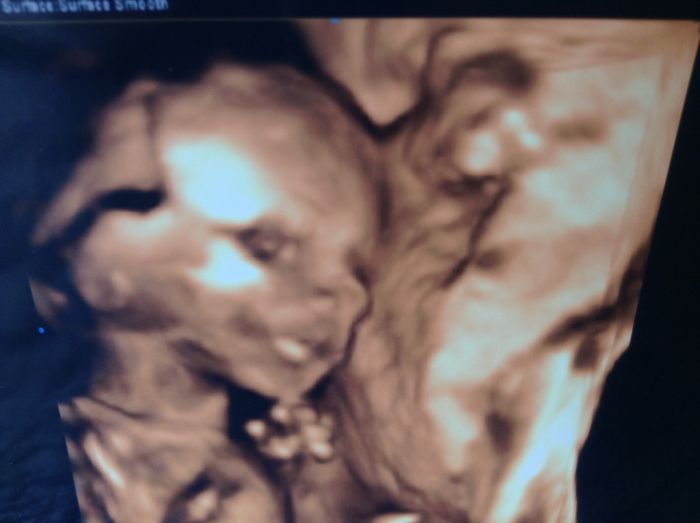

Ahoj všem, tak jsem ve čtvrtek jsem byla na velkém utz. Vše je v pořádku. Potvrdili mi kluka, tak jsem začala nakupovat.... Lehce :). Mám nahoře 1kg. Krvácení z nosu přetrvává. Tehulce, kterou opustil přítel. Když nedoplati alimenty pritel. Doplatí socialka... Teda si myslím. Myslím, ze ten vůl si ani nezaslouží byt zapsán v rodném listě. Jsem moc rada, ze nemusím řešit tvou situaci. Je to určitě psychicky náročné, ale zvládneš to. Ženy jsou silnější. Ohledně bytu. Mas-li klasickou nájemní smlouvu, tak mas ze zákona právo si v bytě zařídit trvale bydliště, i bez souhlasu majitele. Najdi na netu. Příkladam foto z utz. Mějte se pěkně a opatrujte se.

Já byla na velkém utz dneska, a bylo to super, vidět jak je v tom bříšku a mrská rukama i nohama

každopádně vše je ok a na 100% je to kluk